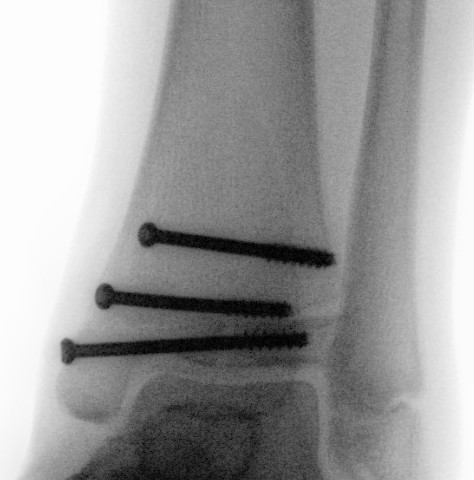

Operative management

Indication

Displaced articular fracture > 2 mm

Technique

AO surgery reference triplanar fixation

JBJS Essential surgical technique triplanar fixation video

Anterior approach between EHL and EDL

- reduce fracture with large reduction forceps

- epiphyseal screw from lateral to medial / medial to lateral

- metaphyseal AP screw into Thurston-Holland fragment

Results

- systematic review of 830 adolescent triplanar fractures

- average age 13

- 17% associated fibular fractures

- premature growth closure / leg length discrepancy 1%